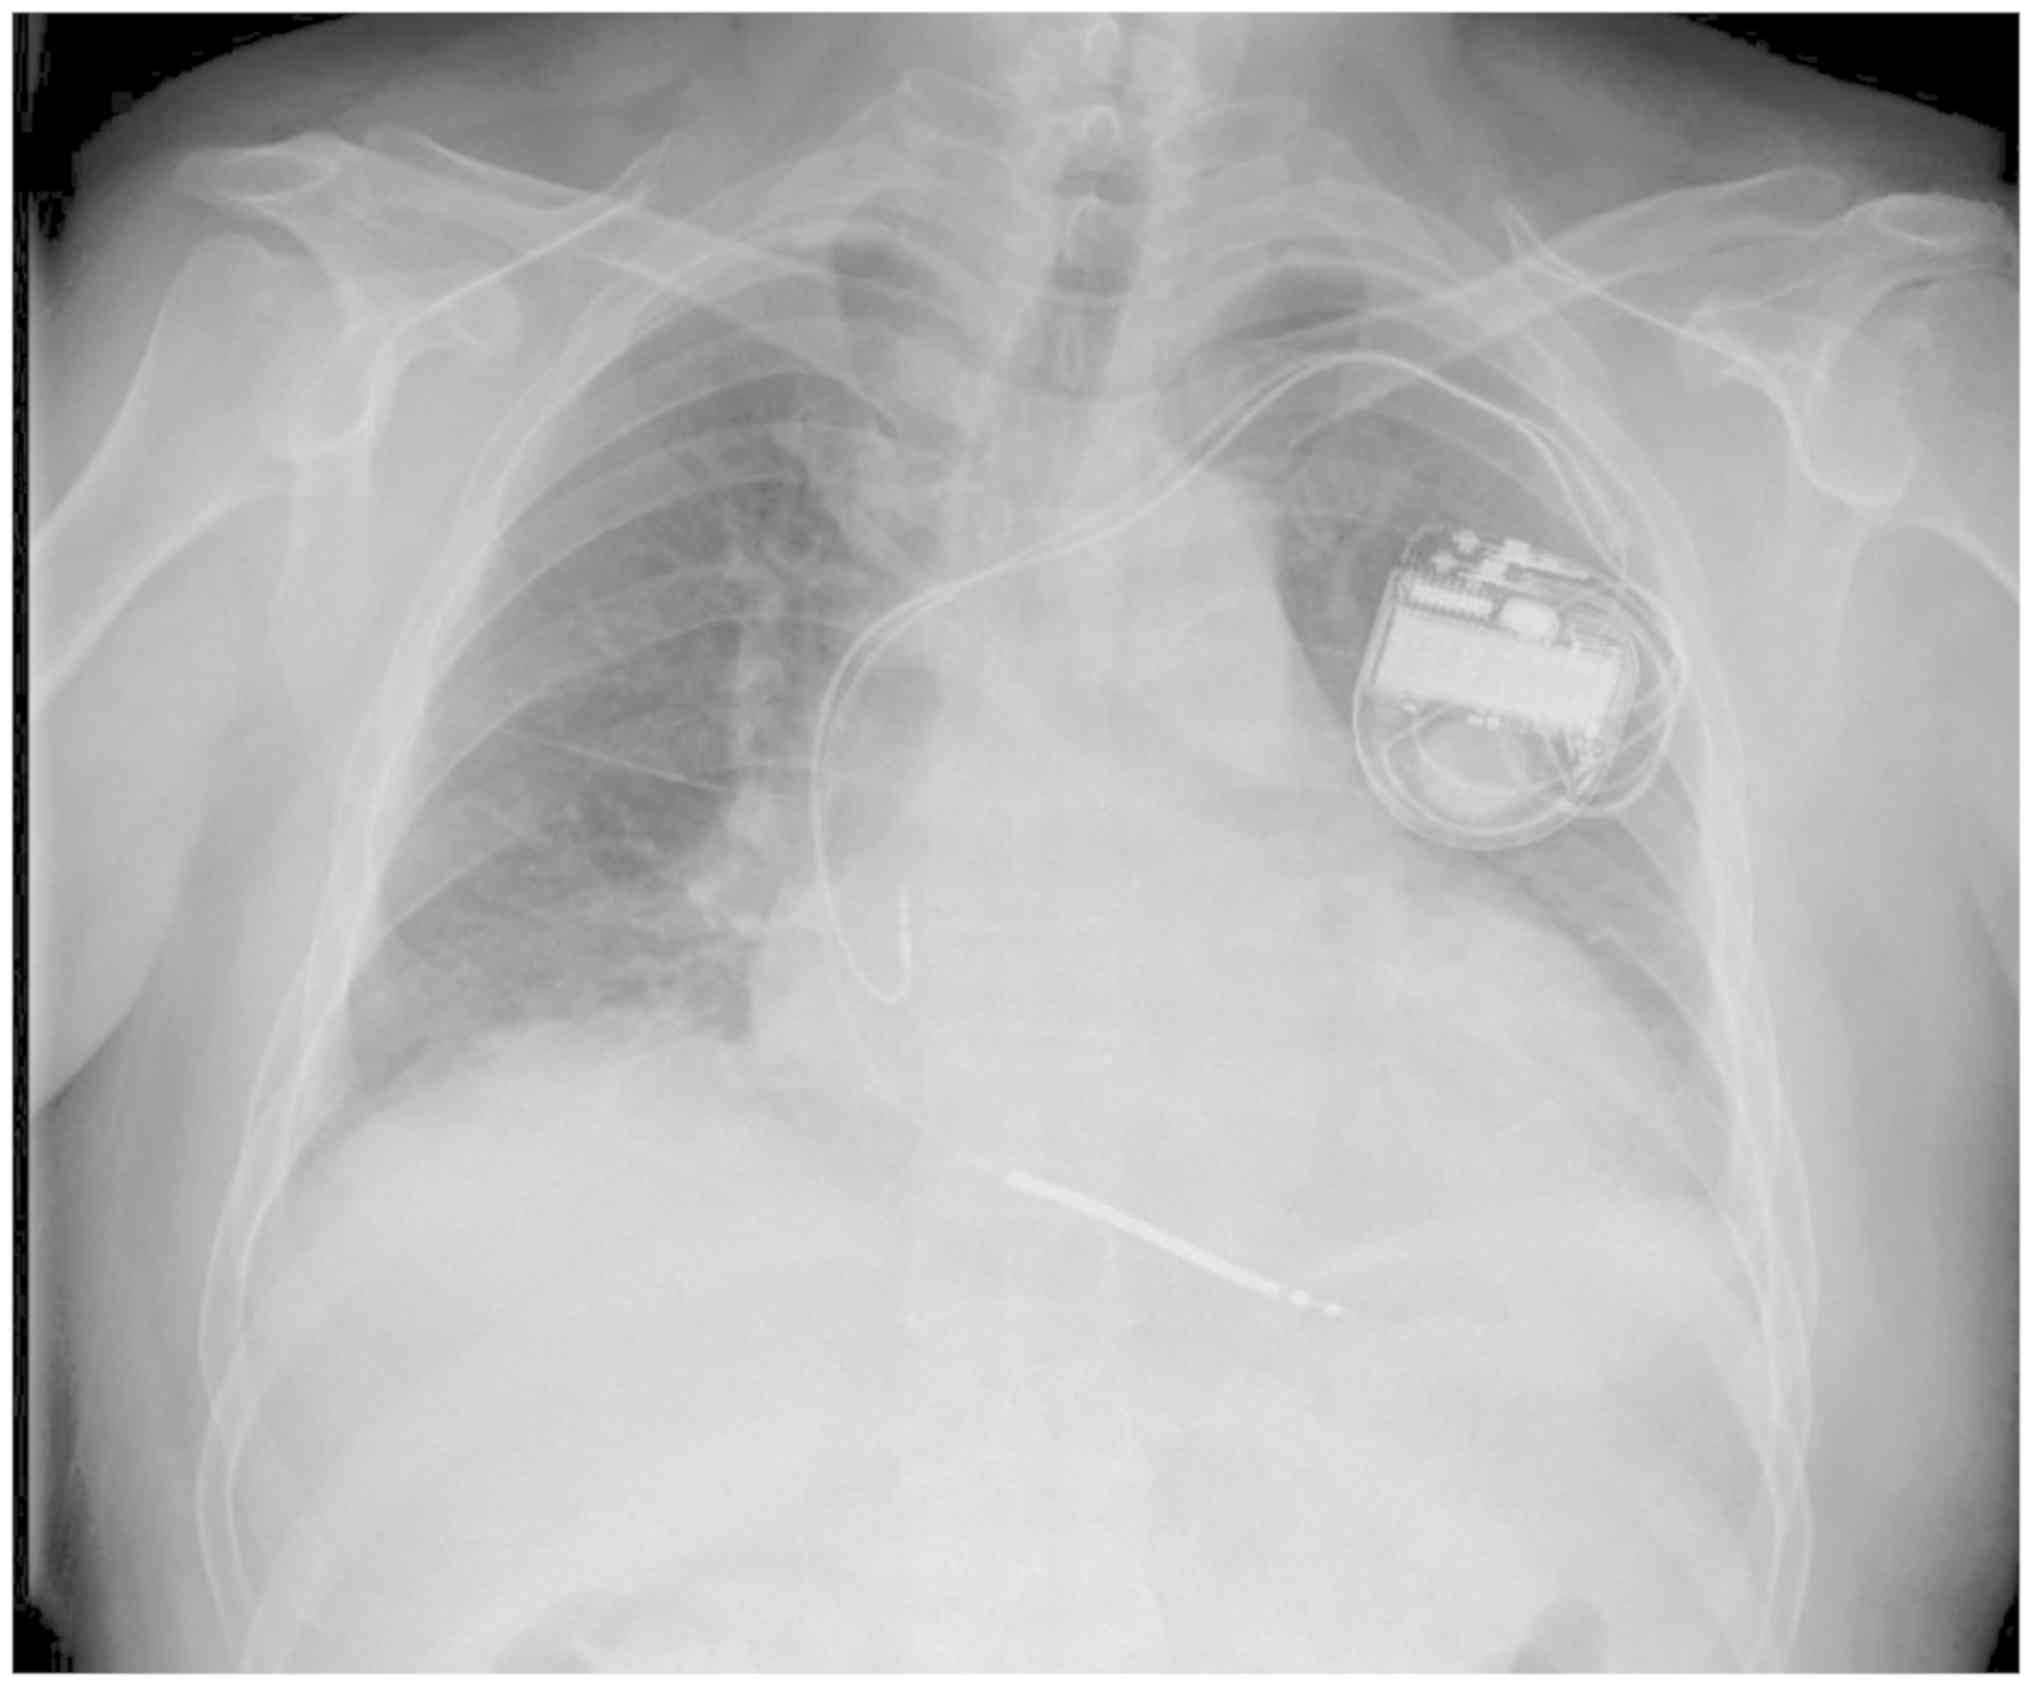

Figure 5.

The X-ray performed on 20th July 2016 indicated that the patient already had a dual chamber cardioverter defibrillator implanted for prevention of fatal ventricular arrhythmias as a part of the treatment course at West China Hospital.